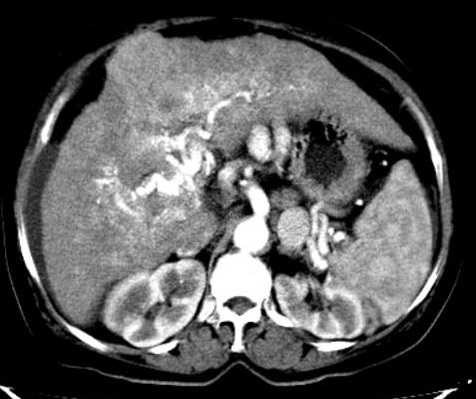

Au temps portale

: il y avait une diminution totale de rehaussement ,

singe de " wash out " . Carcinome hepatocellulaire

.Foie cirrhotique |